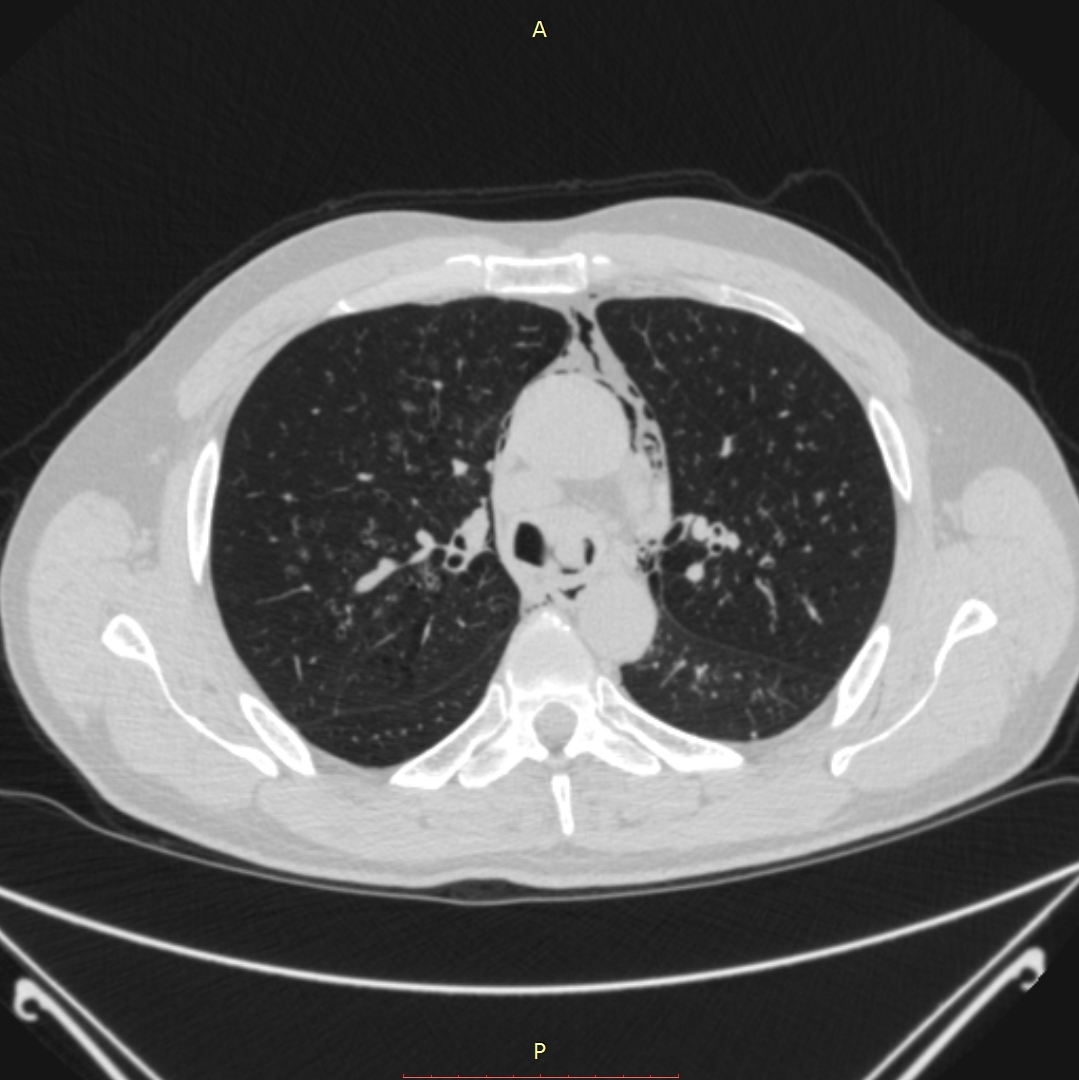

პაციენტი 52წლის მამაკაცი ერთი თვის ანამნეზით. გულმკერდის კტ კვლევით აღმოჩნდა 3,9-3,6სმ ზომის სუბკარინული ქსოვილოვანი კონგლომერატი, რომელიც იჭრება მარცხენა მთავარ ბრონქში და მთლიანად ახშობს მას, ნაწილობრივ ახშობს მარჯვენა ზ/წილოვან ბრონქს. ბიოფსიის მორფოლოგიით დადგინდა ბრტყელუჯრედოვანი გაურქოვანებელი ტიპის კარცინომა. პაციენტის მდგომარეობა დამძიმდა, მოხრჩობის შეტევების გამო ჰქონდა უძილობა. საციცოცხლო ჩვენებით პაციენტს ჩაუტარდა ლაზერული რეზექცია რიგიდული ბრონქოსკოპით, VELASTM 30W ქირურგიული დიოდის ლაზერული სისტემის გამოყენებით. მანიპულაციის დამთავრებისთანავე პაციენტის სუნთქვითი მონაცემები მყისიერად გაუმჯობესდა.

- გულმკერდის კტ (Axial) რეზექციამდე 1 კვირით ადრე 1

მარცხენა მთავარი ბრონქის სანათური თითქმის მთლიანად დახშულია სიმსივნური წარმონაქმნით.

აღინიშნება მარცხენა ქვედა წილის ატელექტაზი.